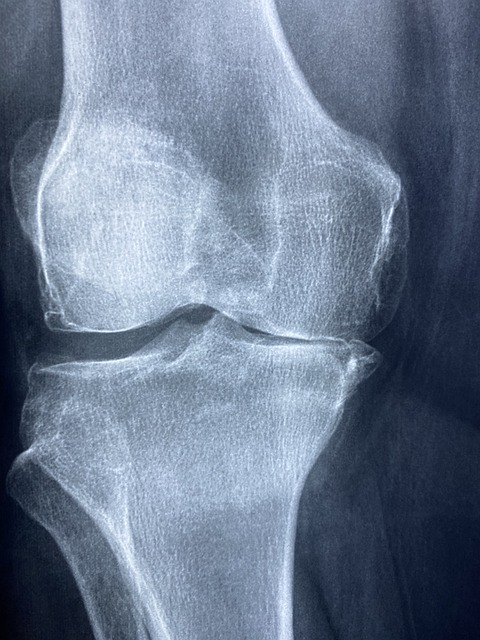

- 비타민 D & 칼슘

- 뼈 건강을 유지하고 골밀도를 증가시켜 관절 부담을 줄여줍니다.

- 햇볕을 충분히 쬐지 못하는 경우 반드시 보충해야 합니다.